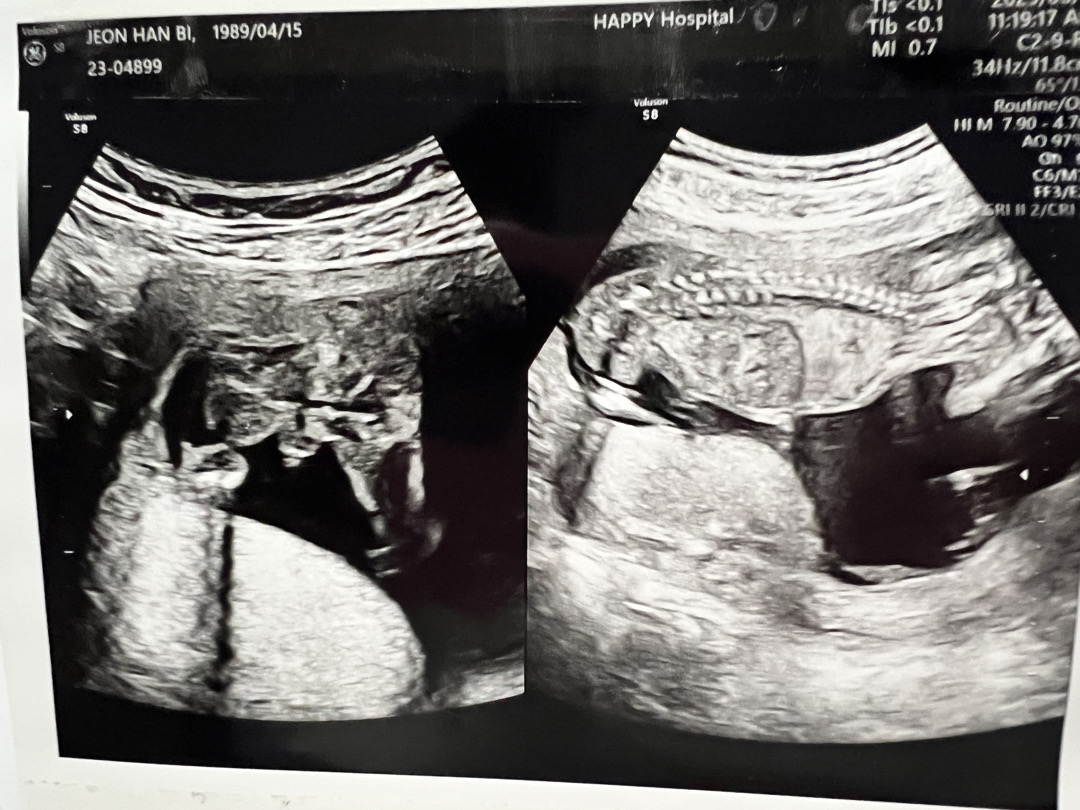

너무나도 듬직한 아들인것같아요!

16주차 의사쌤이 성별을 아직 말씀안해주시네요 ㅜ -ㅠ

사진으로 봤을때는 아들확정일것같은데~ ? 의사쌤은 끝까지 확정을 안주셨어요 ㅠ 궁금하네용 ㅠ

엇 누가봐도 아들이내요..!!!